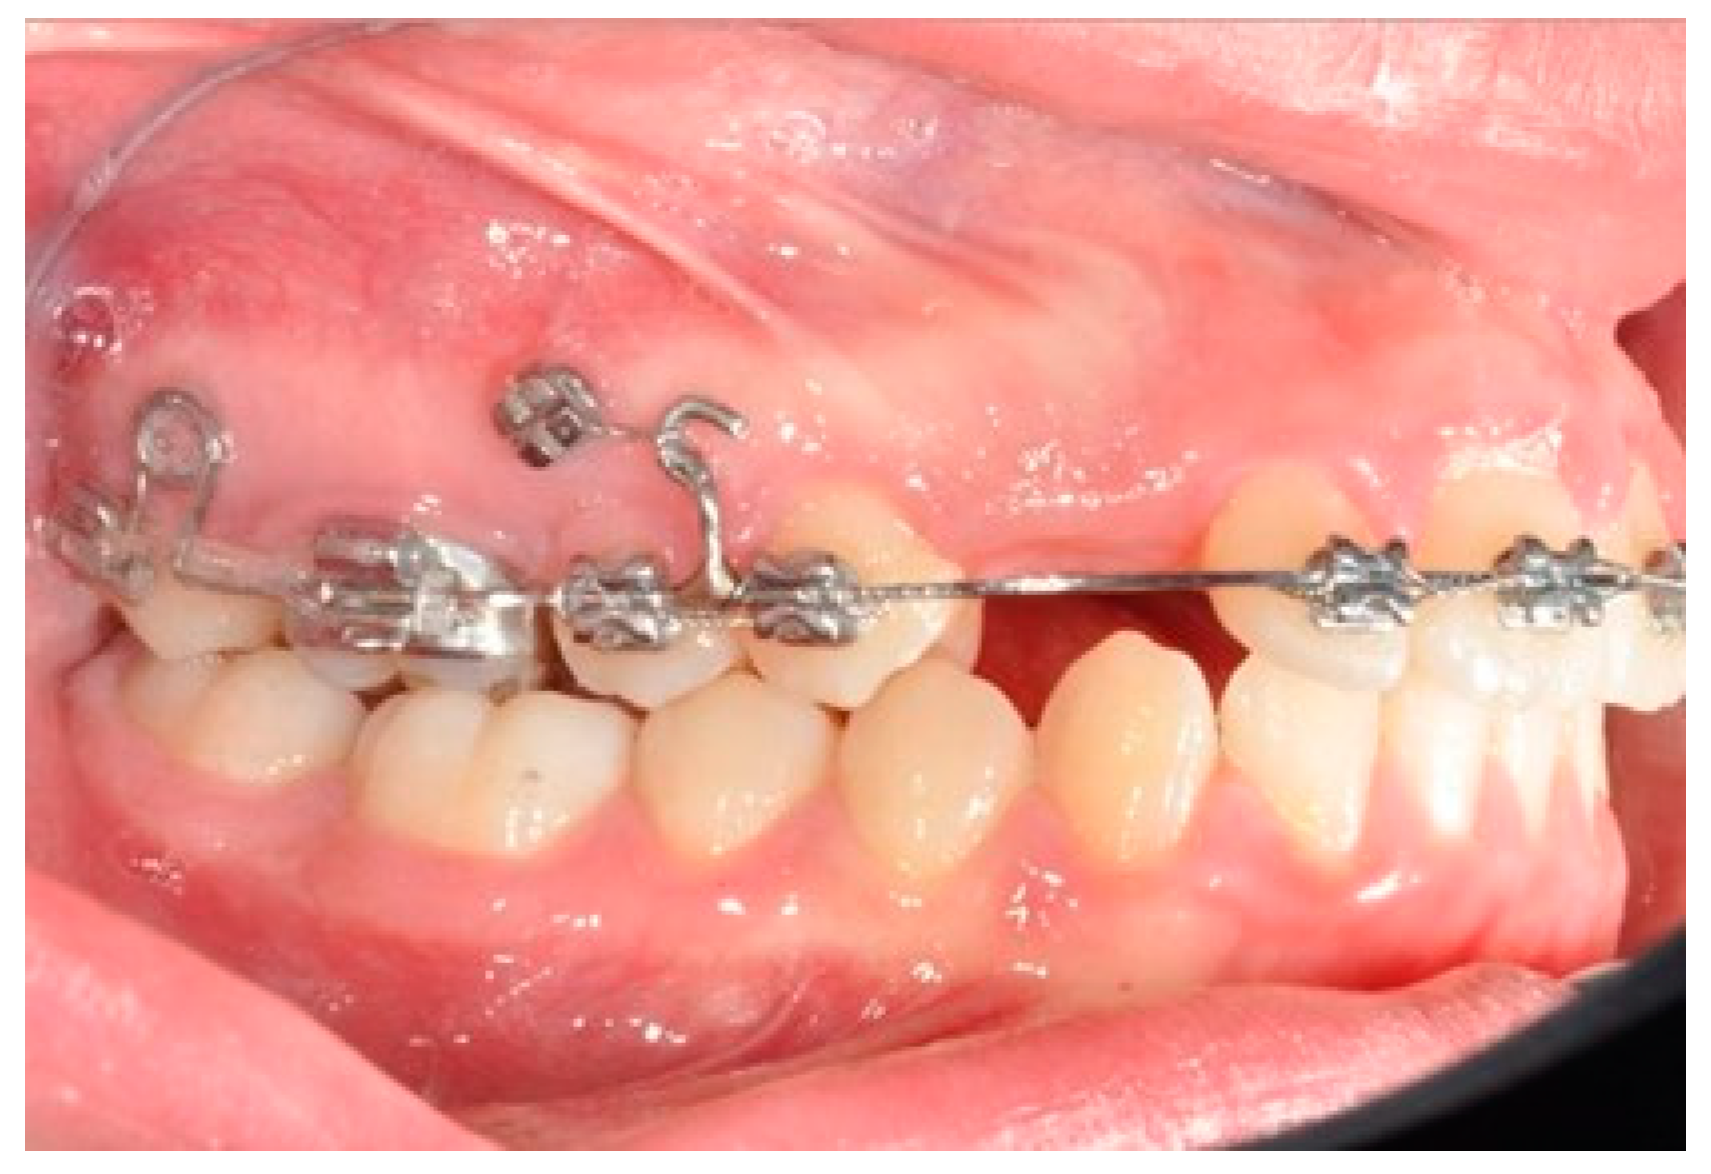

After tad positioning, sequential bonding is applied on the lower arch. An 18 × 0.25 SS arch is shaped, adding a maximum 10° distal tip to the second molar. Hooks are placed between the laterals and cuspids. Third-class elastics (1/4” 6 0z) are placed from the tads to the hooks (Figure 6). The distal tip on the lower second molars will produce a gain of space between molars, with the space needed for the management of the spee curve and the recovery of IMPA.

Figure 6. Molar and premolar distalization strategy: Hooks are placed between the laterals and the cuspids. Third-class elastics (1/4” 6 0z) are placed from the tads to the hooks.